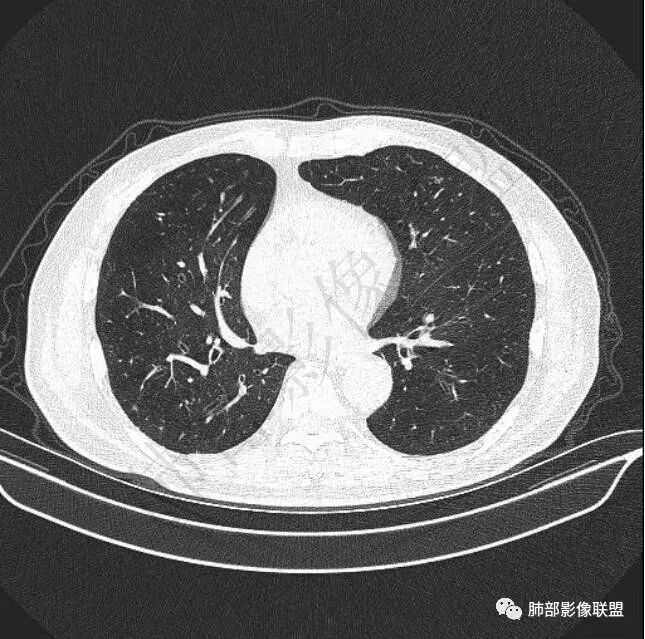

9个月后病灶明显增大,边缘较平直,部分膨隆,锁扣样外观,仍旧缺乏典型深分叶及张力,未见胸膜凹陷。